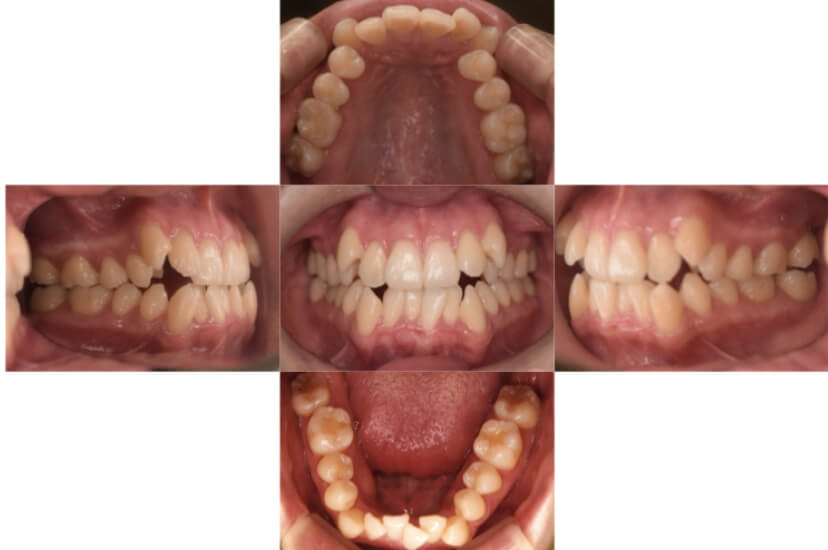

BEFORE

AFTER

上下顎前突、叢生(上下出っ歯、上下の前歯のガタガタ)のケースです。

装置はラビアル(上下表側)で、上下顎の小臼歯を4本抜歯を行っています。抜歯したスペースを使って、上下の前歯の後方移動と叢生(ガタガタ)の改善を行っています。

主訴 前歯のガタガタと口元がでているのが気になる。

年齢・性別 30歳 女性

治療方針 抜歯スペースを利用して上前歯の叢生(ガタガタ)と口元突出の改善

抜歯部位 上下顎左右第一小臼歯

使用装置 ラビアル(上下表側)、顎間ゴム

治療期間 1年11か月